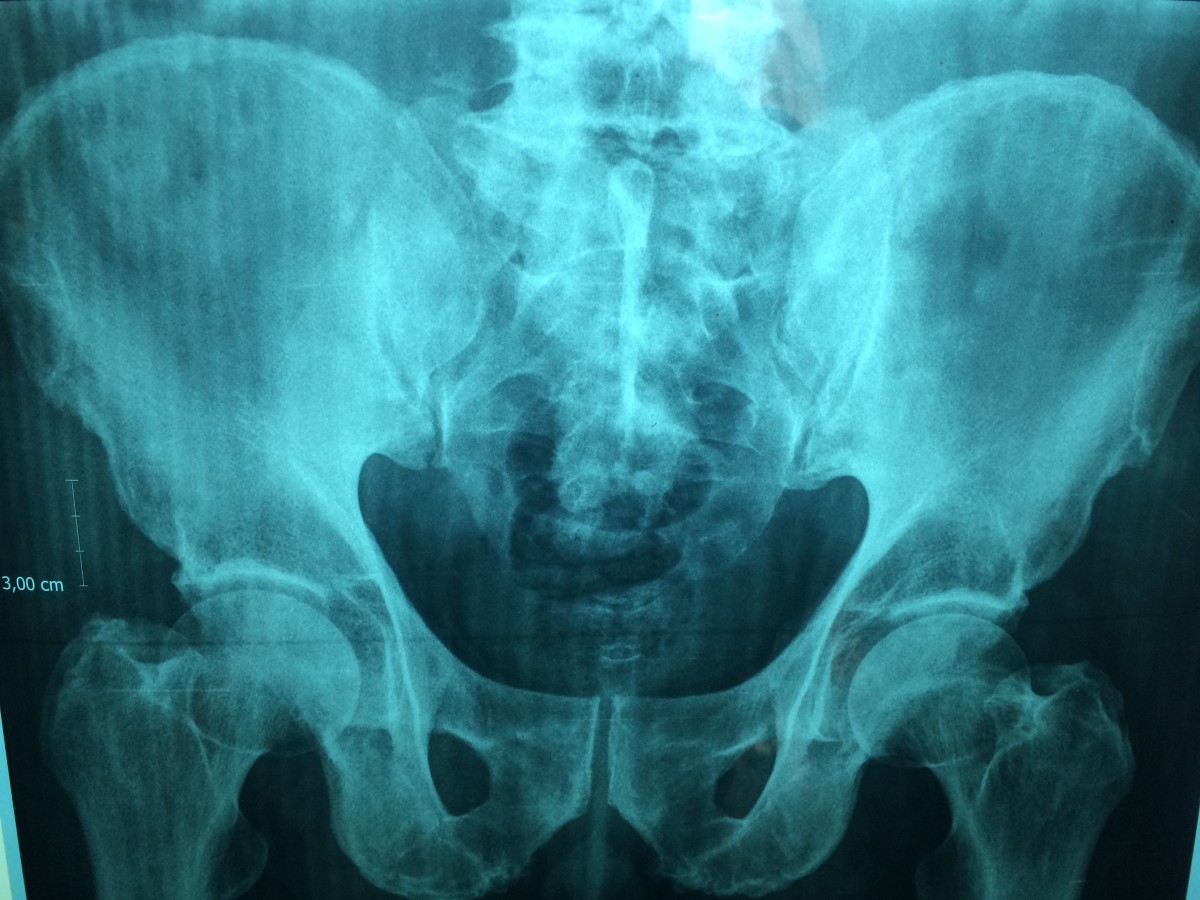

С возрастом у каждого человека возникает повышенный риск повреждения опорно-двигательной системы, поскольку плотность и прочность костей постепенно снижается. Происходящие в нашем организме вполне естественные процессы могут обратиться в неприятное прогрессирующее заболевание — остеопороз. Неутешительная медицинская статистика позволяет судить, что количество больных этим недугом катастрофически растет, что ставит синдром в один ряд с онкологическими патологиями, болезнями сердечно-сосудистой системы и сахарным диабетом по степени распространения.

Остеопороз: статистика и этиологические факторы риска

Системные негативные изменения скелета считаются одним из самых древних недугов. Археологические раскопки и исторические данные позволили установить, что представители индейских племен, жившие 2-3 века до нашей эры, страдали от отдельных форм остеопороза. Характерная для синдрома искривленная осанка четко прослеживается у народов античной Греции и древнего Китая. Тогда наши предки не осознавали природу явления, и потому не пытались его лечить.

На изучение симптоматики и этиологии понадобилось почти 150 лет. Прорыв в медицине начался в 1824 году, когда сэр Эстли Купер, врач из Америки, увидел взаимосвязь между переломом шейки бедра, типичным для пожилых людей, с пористостью и хрупкостью кости. Спустя 50 лет основываясь на его трудах Жан-Мартен Шарко и Альфред Вюльпиан совместно описали остеопорозные патологии. С этого момента хирурги по всему миру стали уделять недугу все больше внимания, наблюдая за изменениями организма и пытаясь найти методы излечения.

Ученые выделяют определенные группы риска, провоцирующие подверженность организма остеопорозу:

- Генетические факторы: низкий вес и хрупкое телосложение, преклонный возраст, принадлежность к европеоидной расе, женский пол;

- Образ жизни: курение, злоупотребление наркотическими веществами и алкоголем, избыточная или недостаточная физкультура, недостаток витамина D;

- Эндокринная предрасположенность: дисбаланс гормонов, сниженная половая активность, раннее наступление менопаузы, бесплодие.

В большинстве случаев заболевание протекает бессимптомно и латентно, однако, бывают случаи, сопровождающиеся острыми болевыми приступами. Долгое время считалось, что избавиться от проявлений синдрома невозможно, но современная медицина это утверждения опровергла. Главное — обратиться к высококвалифицированным докторам на ранних стадиях недуга.